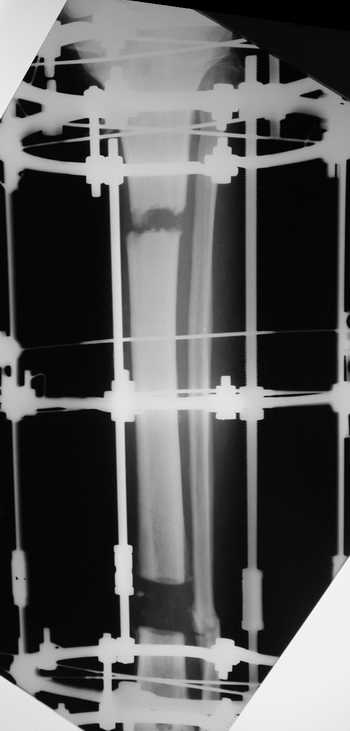

Женщина 46 лет, неудачно лечившаяся по поводу перелома голени в нижней 1\3 сначала в гипсе, поступила через 6 месяцев после остеосинтеза пластиной (рис 1). Имелась деформация в нижней 1\3 голени: варус, антекурвация, наружная ротация, два свища. Удалена пластина, дебридмент мягких тканей,

остеотомия м\б кости, аппарат Илизарова. По рентгенограммам в двух проекциях произведено планирование устранения смещений (рис 2 и 3), между вторым и третьим кольцом установлены 6 телескопических дистракторов Гесапода, данные введены в программу, и далее втечение 10 дней больная подкручивала телескопы согласно выданной компьютером инструкции. По завершению репозиции гексаподные телескопы обратно заменены на обычные штанги от аппарата Илизарова (рис 4 и 5). Еще через две недели забит гвоздь (рис 6, контроль

через 4 месяца).

Мужчина, 33 года, резекция б\б кости по поводу остеомиелита после открытого перелома. Стандартная методика билокального остеосинтеза (рис 1 и 2). В конце удлинения выявилось неудовлетворительное взиморасположение перемещенного фрагмента и дистального отломка (рис 3). Планирование (рис 4).

Адаптация отломков гексаподом за 5 дней (рис 5). Замена гексапода на обычные штанги (рис 6 и 7)